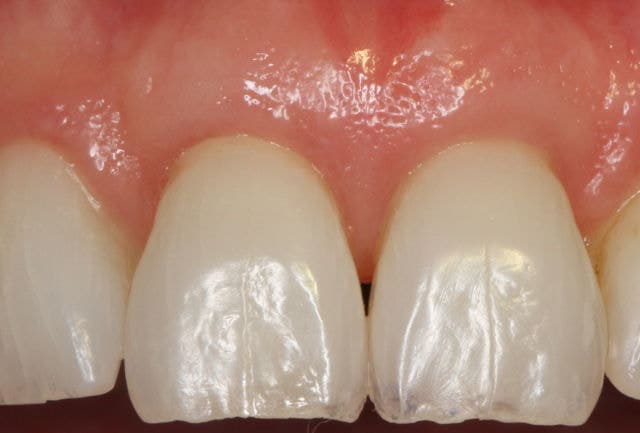

After

Patient: Jill